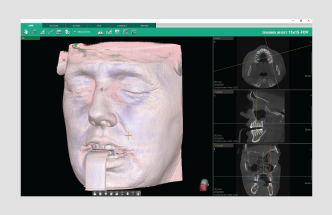

• Soft-tissue bone mode

• Soft-tissue mode

FEATURING VATECH’S VIRTUAL CONSULTATION TOOL

With over 200 unique animations, VCT gives you the tools to not

only educate patients on treatment plans, but also show how

this plan is relevant to their specific case.